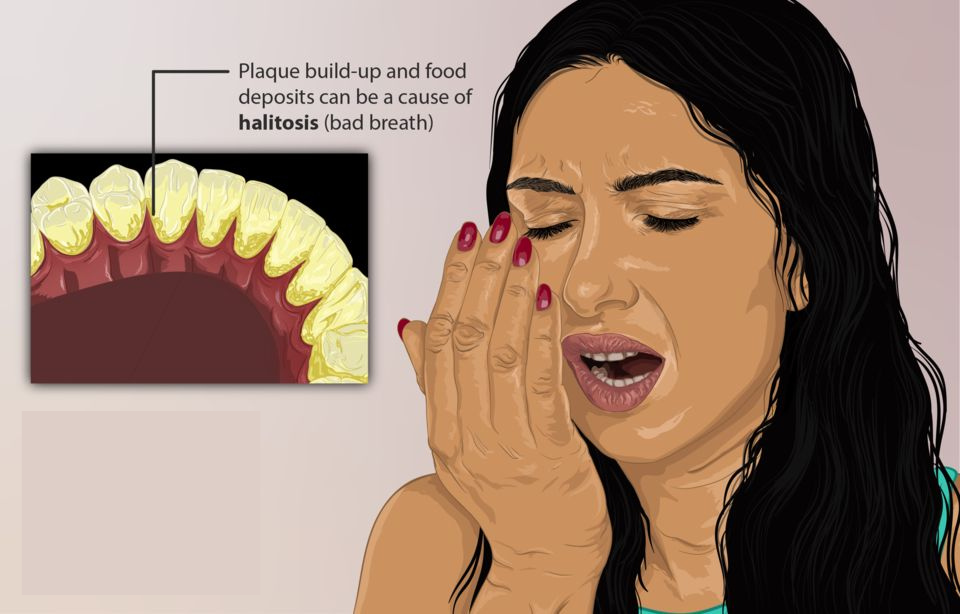

Yusuf,” he said, “there are some dirt and bacteria your toothbrush will never be able to remove.

When you leave them there, they harden into plaque, and over time, that plaque turns into tartar.

That’s why many people have bleeding gums or tooth decay even though they brush daily.”

Plaque hides between teeth and along your gumline where toothbrush bristles can’t reach

Missed Plaque Hardens Into Tartar

Plaque hardens into tartar that brushing or floss sticks can’t remove and once hardened, tartar can only be removed by a dentist.

Wave Bad Breathe Goodbye

- Completely removes odor

- Improves tastebud

- Keeps your breath fresh all day